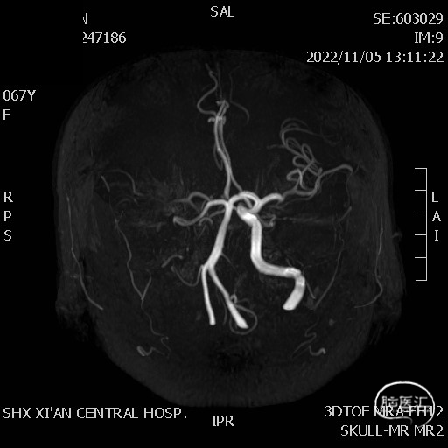

术前影像检查

MRA:右侧大脑中动脉闭塞。

DWI:右侧额顶叶、岛叶、基底节区新鲜梗死病灶。

脑血管造影:3型主动脉弓,右侧颈内动脉起始段闭塞,后循环及左侧颈内动脉均未向左侧颈内动脉供血区代偿。